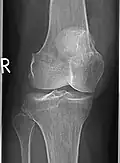

Korrespondierendes Röntgenbild, hier ist der Tumor fast nicht abgrenzbar

Riesenzelltumoren finden sich in etwa 3/4 der Fälle an den Extremitäten und in einem Viertel der Fälle am Rumpf. An den Extremitäten sind Riesenzelltumoren weitgehend auf die Epiphyse der langen Röhrenknochen beschränkt und dort neben dem Chondroblastom der häufigste gutartige Knochentumor. Durch die Lage in der Epiphyse sind sie somit fast immer gelenknah. Die häufigste Lokalisation ist in der Hälfte aller Extremitäten-Riesenzelltumoren das Kniegelenk mit der distalen Femurepiphyse in 34 % und der proximalen Tibiaepiphyse in 29 %.[3] Riesenzelltumore können, auch wenn deutlich seltener, im Bereich der Wirbelsäule auftreten.[4]